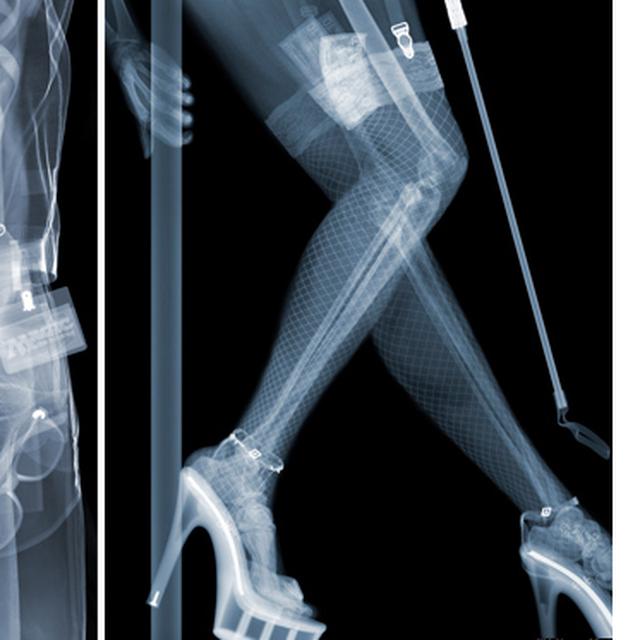

Unik Fotografi Dari Sinar X Ray Karya Nick Veasey Lifestyle